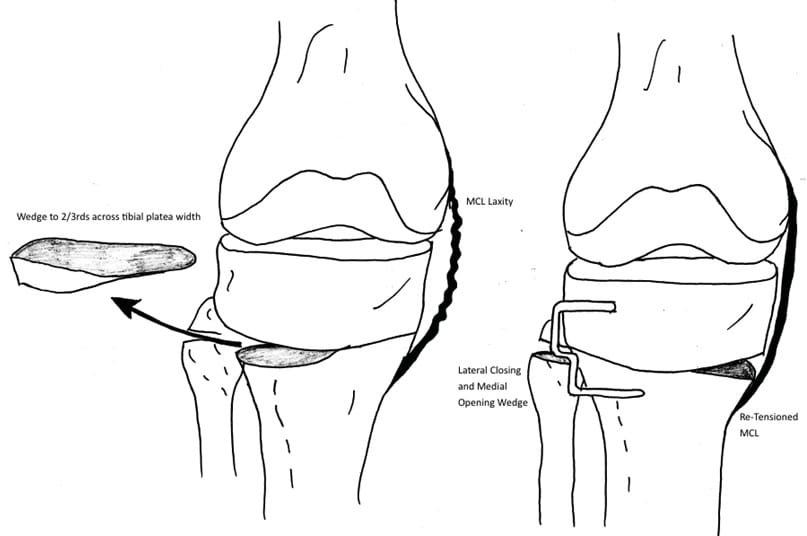

In patients who have more than 3mm of MCL laxity with valgus stress (pseudolaxity), we make two modifications to the technique to restore tension to the MCL (Figure 6). Firstly, the initial osteotomy is completed through the medial cortex, releasing cortical and periosteal constraints but leaving the MCL intact. Secondly, the apex of the second, distal osteotomy is aimed short of the medial cortex (only two-thirds of the transverse width across the tibia). When the leg is now forced into valgus, the effect is a simultaneous closing wedge lateral osteotomy, and an opening wedge medial osteotomy. The mechanical axis is still shifted laterally, and the tension in the medial collateral ligament is restored. No graft is necessary as the medial wedge is small (Figure 7).